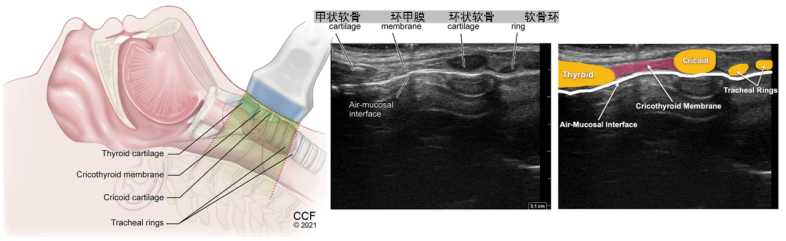

二、气道解剖及常用切面

从气道解剖结构来看,一般以环状软骨为界,区分上呼吸道和下呼吸道,环状软骨之上的鼻腔、咽和喉组成了上呼吸道,环状软骨以下的气管、主支气管和肺组成了下呼吸道。气道超声扫查的范围就是从下颌到胸骨上的位置(图1),包括上呼吸道的舌、会厌、甲状软骨、声带,以及下呼吸道的环状软骨和各个软骨环。

与舌骨上切面相比,舌骨下切面会多一些,在横切面可以看到甲状软骨、环状软骨及软骨环,在矢状面可以看到甲状软骨、环状软骨和各个软骨环的精确定位,矢状面的标记点指向头侧,横切面的标记点指向患者右侧(图7)

图7  舌骨下常用切面

(6)环甲膜矢状切面:将探头从横切面顺时针旋转90°改为纵切后,在图像上从左到右依次可以看到甲状软骨、环状软骨和一些椭圆形呈串珠状的软骨环,此时就可以精确定位每一个软骨环(图14)

图14  环甲膜矢状切面